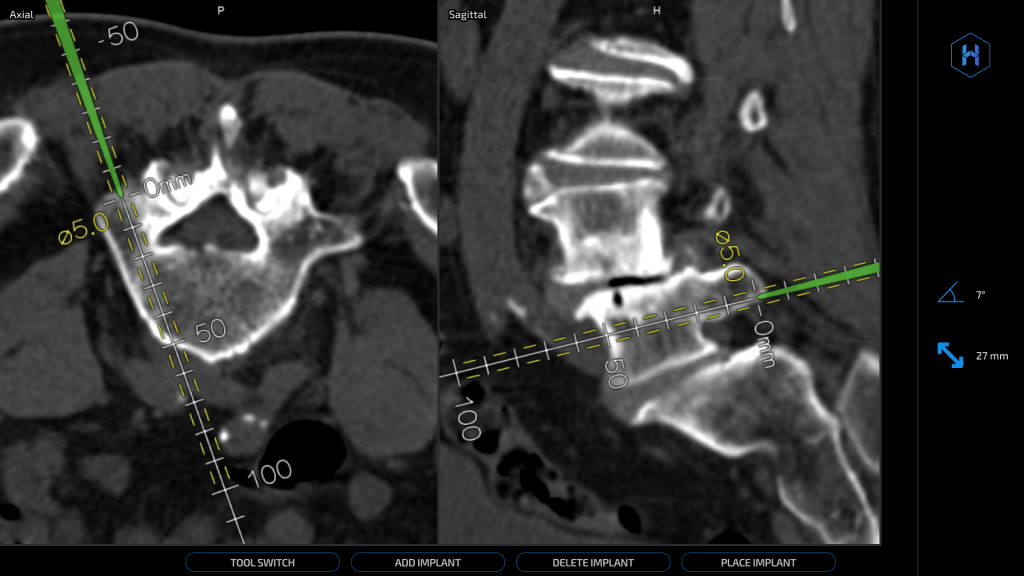

Designing and implementing three new sets of DICOM series (Summary, Sagittal, Axial) enhanced by AI to be viewed alongside original images, optimizing visual appeal and user experience through collaboration with physician consultants and detailed design systems, ultimately bridging the gap between machine learning outputs, customer requirements, and business goals.

Developer Handoff

The final step in implementing the designs in our product would be to equip our development team with the visual criteria and visual assets. In addition to detailed mockups such as the one below, I presented an interactive Design Systems in-depth technical presentation that taught our front-end developers how to interact with our Figma design system and pages.